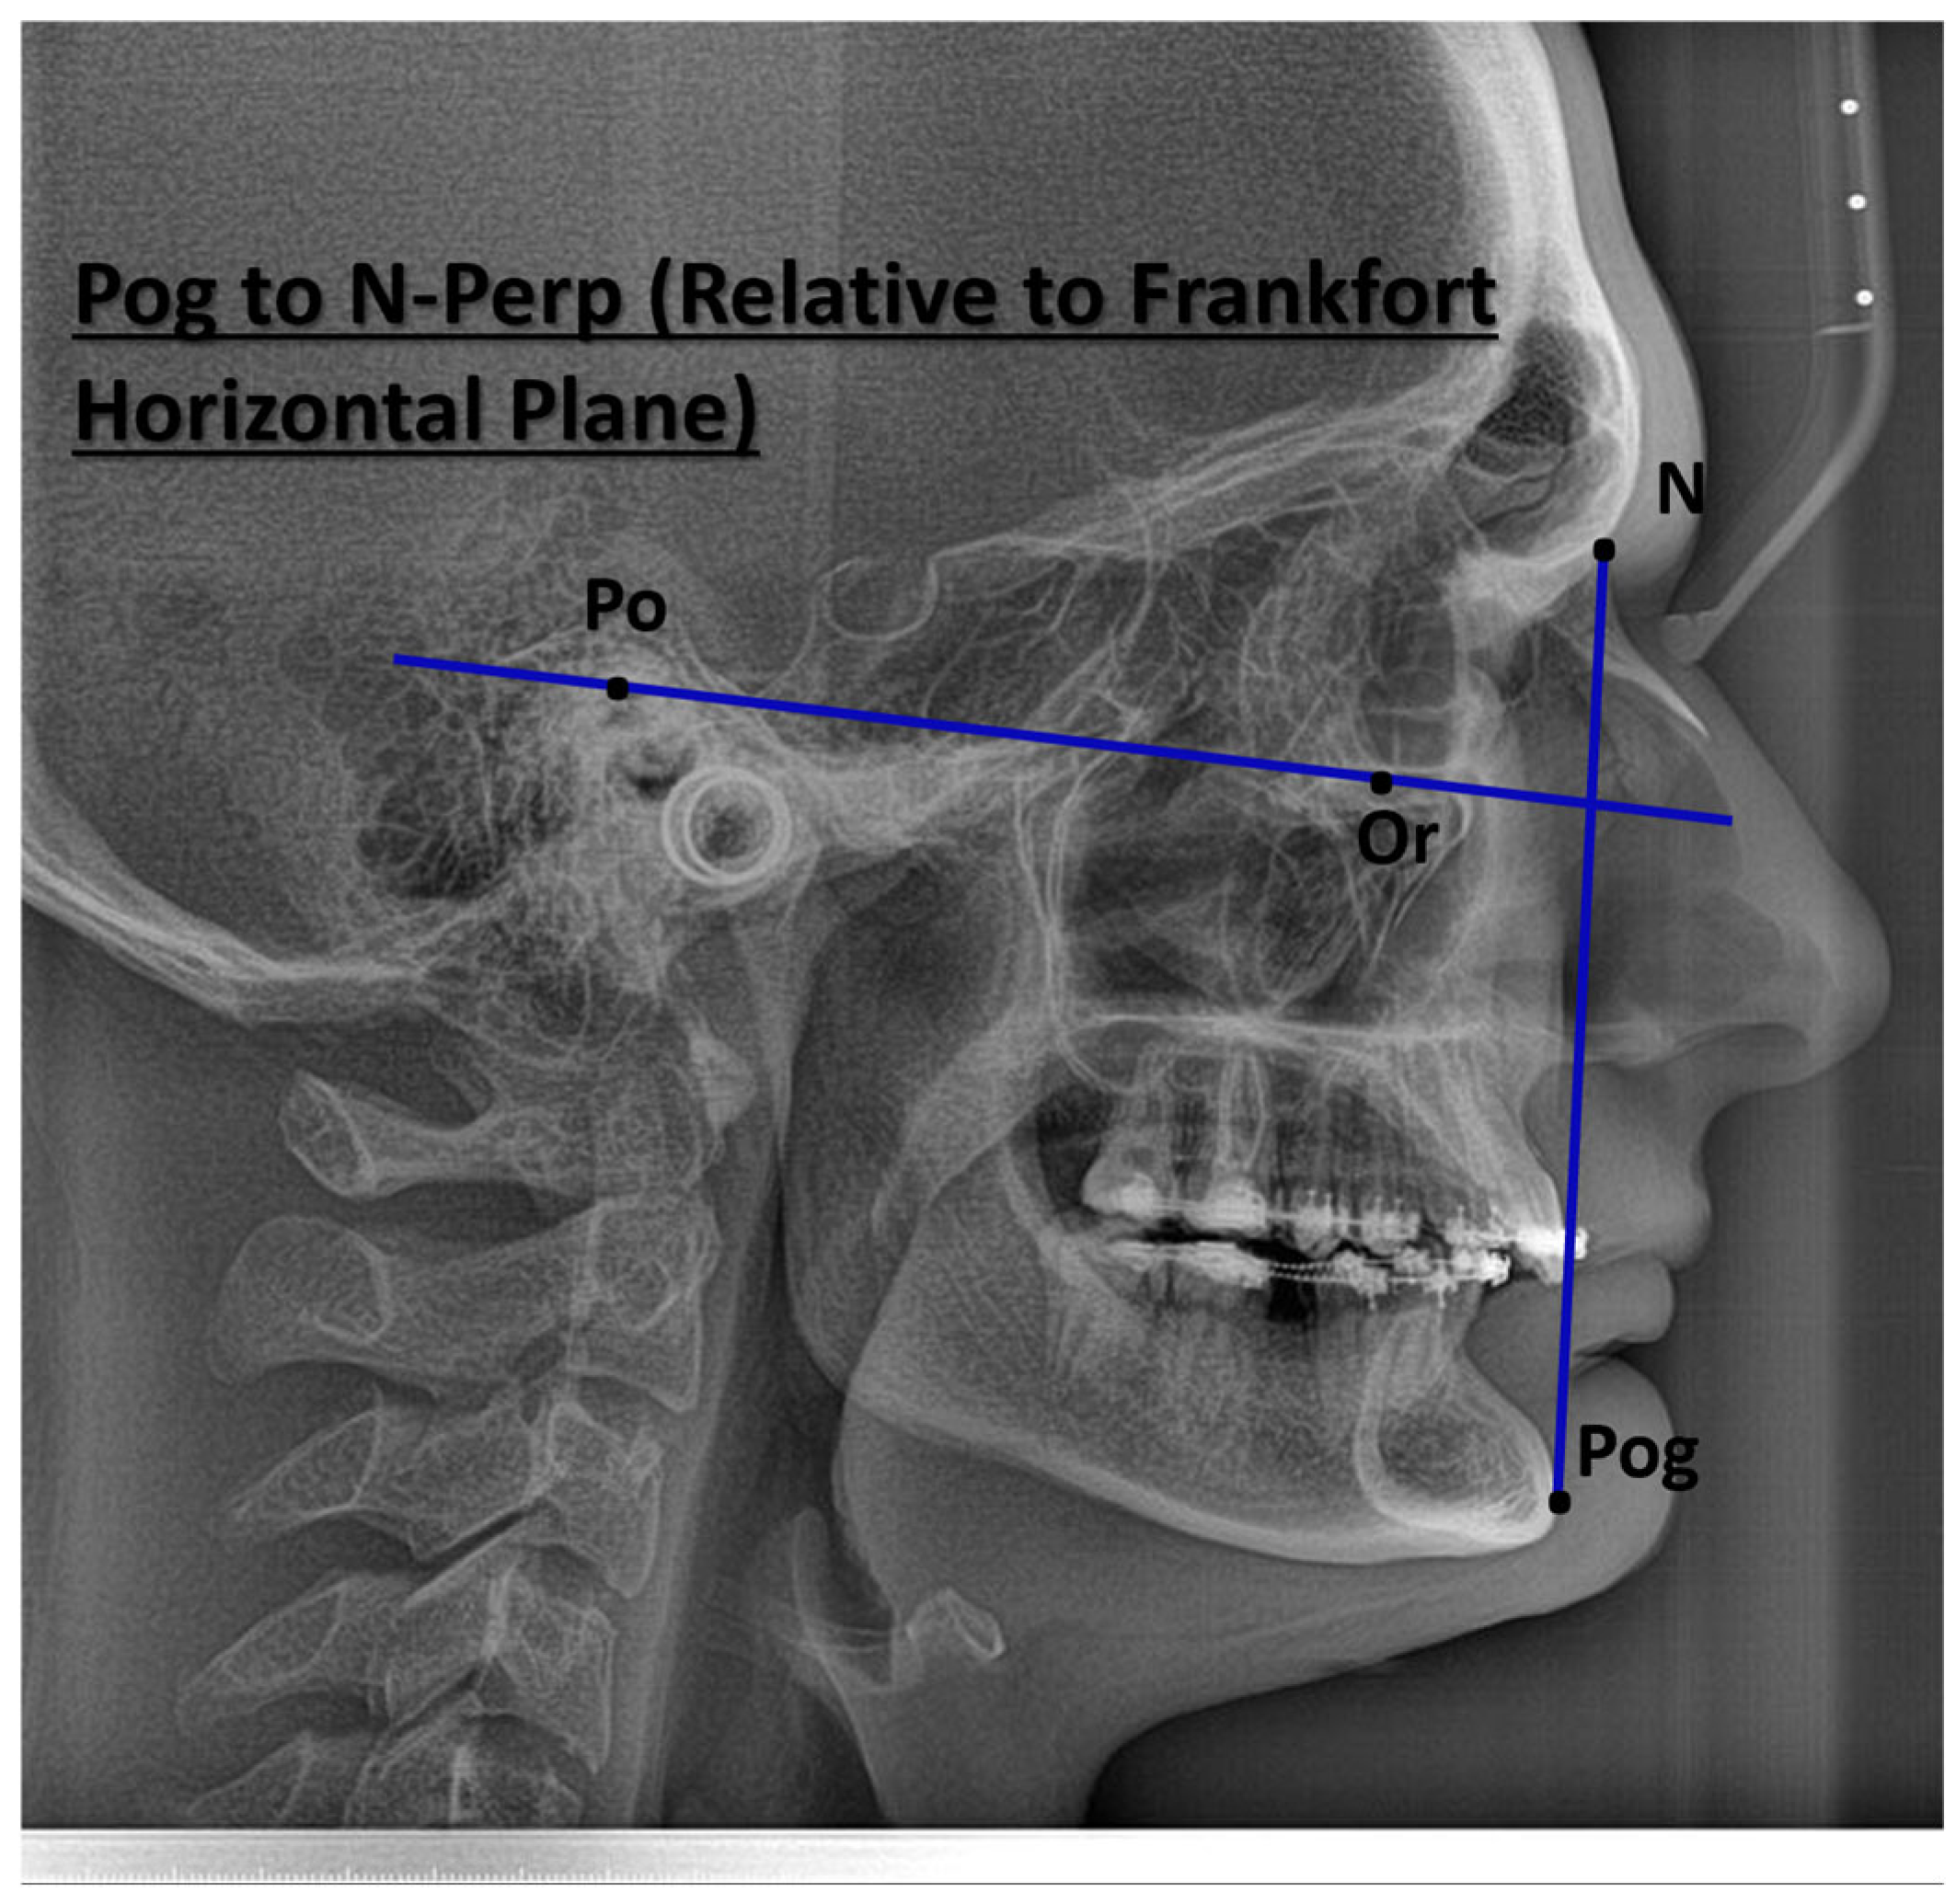

| Characteristic | Preoperative Median (IQR) | Postoperative Median (IQR) |

|---|---|---|

| Demographics | ||

| Age (years) | 28.0 (24.0, 33.0) | – |

| Sex, n (%) | Female: 11 (44%) Male: 14 (56%) | – |

| Skeletal parameters | ||

| SNA (°) | 83.6 (79.9, 84.9) | 86.3 (80.4, 89.0) |

| SNB (°) | 83.5 (76.8, 87.2) | 84.0 (81.0, 86.0) |

| ANB (°) | 0.9 (−4.9, 5.3) | 3.0 (−0.2, 4.5) |

| Pogonion to N-Perpendicular FH (mm) | 1.87 (−0.94, 2.31) | 1.4 (0.4, 2.6) |

| Dental parameters | ||

| U1–NA (°) | 26 (21, 28) | 22 (19, 29) |

| L1–NB (°) | 24 (17, 27) | 25 (19, 30) |

| Soft tissue parameters | ||

| Nasolabial angle (°) | 102 (92, 114) | 105 (91, 117) |

| Facial convexity (°) | 0 (−12, 7) | 2 (−6, 5) |

| Variable | Mean Difference | SE Difference | t | df | p-Value |

|---|---|---|---|---|---|

| SNA (°) | −3.123 | 1.24 | −2.511 | 24 | 0.019 |

| SNB (°) | −1.147 | 1.41 | −0.811 | 24 | 0.426 |

| ANB (°) | −1.980 | 1.00 | −1.977 | 24 | 0.060 |

| Pogonion to N-Perpendicular FH (mm) | −1.571 | 1.21 | −1.296 | 24 | 0.207 |

| U1–NA (°) | 0.465 | 1.87 | 0.249 | 24 | 0.806 |

| L1–NB (°) | −2.968 | 1.55 | −1.915 | 24 | 0.067 |

| Nasolabial angle (°) | −6.950 | 8.83 | −0.787 | 24 | 0.439 |

| Facial convexity (°) | −0.502 | 4.12 | −0.122 | 24 | 0.904 |